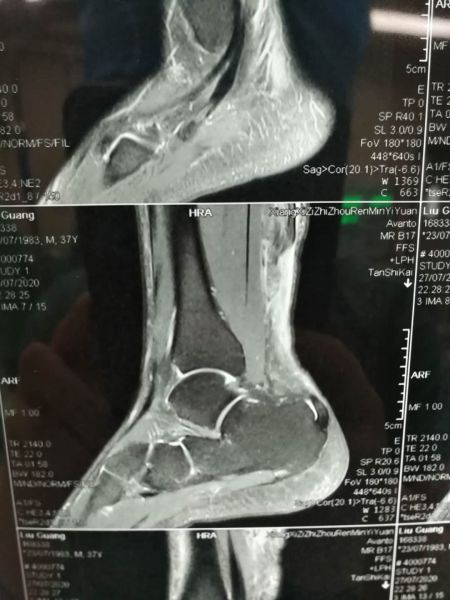

家住怀化的刘先生,今年37岁,是位篮球运动爱好者,由于发力不当在运球过程右脚受伤。入院后,经过核磁共振检查,诊断为“右跟腱断裂”,建议尽快手术治疗。

入院检查结果显示“右跟腱断裂”。